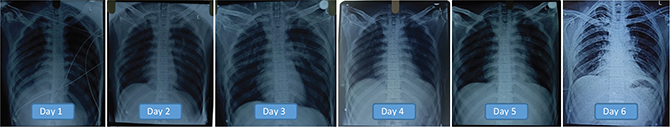

The cardiac surgeon recommended replacing the intercostal tube drainage bag with a bottle and coupled to 30-cm H2O-negative suction. The tele-ICU team reviewed images and recommended daily chest X-rays. And the drain output gradually decreased in tandem with good lung expansion. The tele-ICU team evaluated the patient’s spontaneous breathing, carefully examining the tidal volumes, calculating the rapid shallow breathing index (RSBI), and advising the peripheral center team when to remove the patient from the ventilator. The ability to view the patient and the ventilator at the same time with the help of the PTZ cameras helped the intensivist accurately analyze the spontaneous breathing trial and RSBI.

The patient’s breathing gradually improved. On Day 5, the patient was extubated following 4 days of mechanical ventilation after ensuring good lung expansion and evaluating spontaneous breathing using the rapid shallow breathing index (Figure 6). A repeat HRCT confirmed that lung expansion was adequate. Oxygen was gradually tapered and then stopped, and the patient was discharged after 10 days.

Fig. 6. The patient’s X-rays (day 1 through day 6) reveal gradual improvement. On Day 5, the patient was extubated following 4 days of mechanical ventilation.